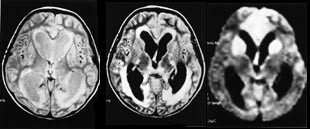

Diagnostikken ved både spinale og intracerebrale infeksjonssykdommer er betydelig bedret med MR i forhold til CT (23). Når det gjelder infeksjoner i hjernehinner kan MR gi bilder som det tidligere ikke var mulig å fremstille (fig 8). Særlig ved infeksjoner i hjernevevet kan det være nyttig å bruke flere forskjellige sekvenser. Diffusjonsvektet sekvens kan for eksempel vise iskemiske forandringer som ikke trer frem ved de mest vanlige sekvenser (fig 9).